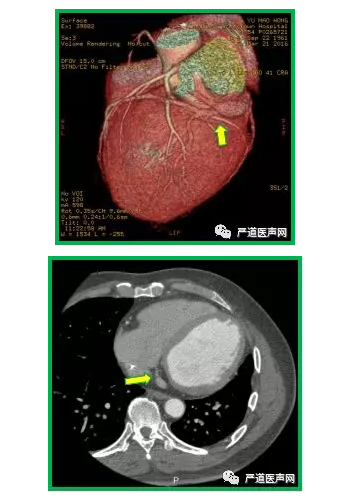

寻找CS开口方案五:术前行冠状静脉CTA

● 适用情况:

➛新增左室导线

➛重置左室导线

● 难点:

➛放射技师需掌握延迟扫描时间

➛心功能差患者显影不佳

➛较小分支显影不完全